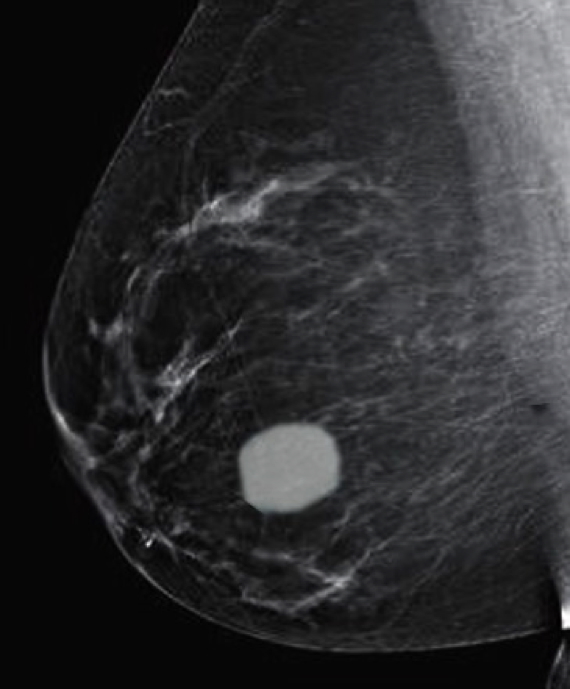

- Most common benign tumour of the breast

- Usually affects women aged 20–40 years

- Mammographic density or calcifications

- Size: usually <5cm

- Surgical excision is curative but often unnecessary

2. Fibroadenoma of the Breast, Lori A. Erickson, MD; Beiyun Chen, MD, PhD, DOI: https://doi.org/10.1016/j.mayocp.2020.08.040